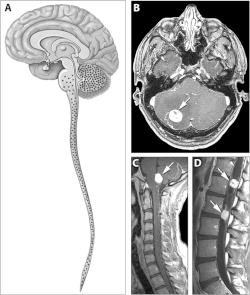

Hämangioblastome sind häufig im Bereich des Kleinhirns, des Hirnstamms oder des Rückenmarks lokalisiert, kommen selten aber auch im Großhirn vor. Im Bereich der Netzhaut des Auges auftretende Hämangioblastome werden häufig fälschlicherweise als retinale Angiome bezeichnet.

In der radiologischen Bildgebung stellen sich Hämangioblastome als kontrastmittelaufnehmende, häufig pseudozystische Raumforderungen dar.